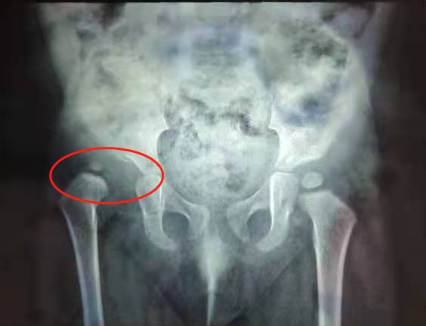

今年元旦,小儿骨科史迎春主任坐门诊时,山东的一对夫妻带着1岁的女童走进了诊室。“主任您好,我们家孩子1岁了,刚学会走路,我们发现她走起路来,右腿总是一瘸一瘸的。”史主任让孩子走几步瞧瞧,果然发现孩子的右腿行走姿势不正确,根据临床经验,他初步断定女童患有单侧先天性髋关节脱位,通过X光线拍片检查证实女童确实患有先天性髋关节脱位(右侧)。

X光线片

X光线检查显示女童右侧股骨头完全脱出离髋臼,向外上方移位,史主任考虑采用切开手术的方式,将髋臼周围的肉芽组织清理掉,再通过石膏外固定帮助复位。女童家长同意手术方案,次日,史主任手术团队为女童进行了切开复位+髋人字石膏外固定术,通过手术改善髋臼和股骨头的匹配关系,为发育差的髋关节提供了正常的发育环境。